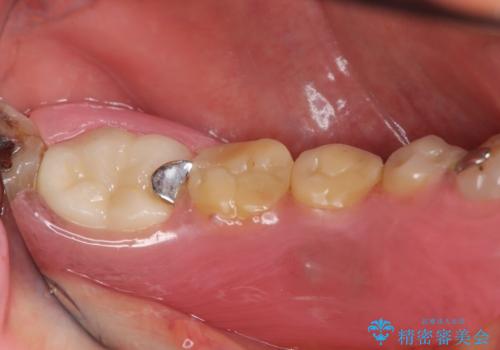

- 定期的に本院に通院されている患者様で、前歯の揺れがあると相談されました。下の奥歯が左右合わせて3本喪失されており、噛み合わせの負担が前歯にも集中していることを説明しました。右下6番の歯に関しては、事前の診査で十分な骨量がありましたのでインプラントを1本埋入しました。左下5番・6番にも本来はインプラントを埋入したかったのですが、骨量が十分でなく、骨を増やす処置をすると神経が近くリスクがあることから、審美性に配慮した金属のばねが見えないノンクラスプデンチャーを製作しました。また、このとき入れ歯を支える左下7番に根尖病変がありましたので、根管治療も行っております。(根管治療は当院院長で専門医を持つDr.林が担当しています。)治療終了後、約1年が経過しましたが、問題なく経過しており患者様も喜ばれていました。